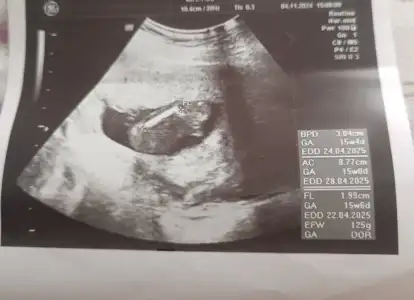

Kızlar dün doktorum cinsiyet tahmini yaptı kız büyük ihtimal ama 3 hafta sonra tekrar bakarız kesin o zaman belli olur dedi ben hep erkek hissediyordum ama kız olunca çok mutlu oldum hissiyat olarak sadece erkek olucak kesin diyordum ama yanıldım sanırım sizce cinsiyeti değişicek mi çok heycanlıyımUltrason fotoğrafını asağıya ekliyorum Eki Görüntüle 3233482

Kızlar dün doktorum cinsiyet tahmini yaptı kız büyük ihtimal ama 3 hafta sonra tekrar bakarız kesin o zaman belli olur dedi ben hep erkek hissediyordum ama kız olunca çok mutlu oldum hissiyat olarak sadece erkek olucak kesin diyordum ama yanıldım sanırım sizce cinsiyeti değişicek mi çok heycanlıyımUltrason fotoğrafını asağıya ek

Ultrason resmime bakar mısınız benimki ne sizce